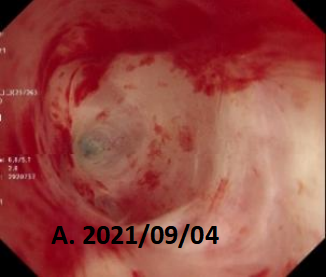

镜到之处,目之所及:左主支气管开口呈瘢痕样狭窄,远端支气管闭塞。难怪CT上只看到一边的肺,现在真相大白了!患者目前左肺开口处被肺瘢痕完全封堵,形同虚设,只有右肺可以用。

图2 支气管镜下表现